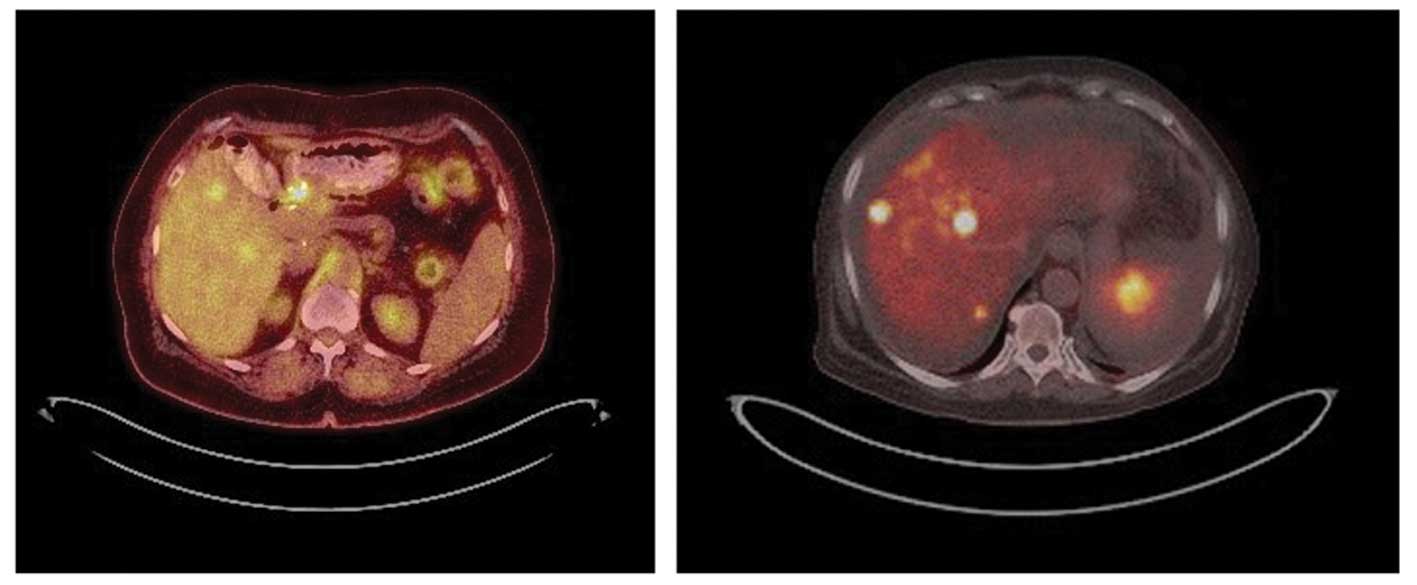

Although conventional imaging with ct and mr remains the main imaging modality recent times have seen an increase in the applications of petct in the evaluation of pancreatic malignancy.

Pet ct scan pancreatic cancer. The bright spot in the chest seen best on the pet and ct pet scans is lung cancer. Pancreatic malignancy carries a poor prognosis and is the fourth leading cause of cancer related deaths in the united states. The image on the right is a combined ct pet scan.

Pet can detect extremely small cancerous tumors subtle changes of the brain and heart and give doctors important early information about heart disease and many neurological. Fdg petct scan pet has been approved by cancer care ontario since 2011 for pancreatic cancer patients who have potentially resectable disease. If the pet scan of the tumor turned cold following chemotherapy even if the ct scan was the same that highly predicted that when a pathologist looked at the tumor following surgery that cancer.

With the ge discovery petct 600 scanner a four dimensional ct scanner that produces detailed cross sectional x ray images of structures within the body our radiologists are better able to plan treatment in accordance with patients. Herein we reviewed the outcomes of pet in the disease staging and management of patients with pancreatic. Petct which is a combination of positron emission tomography pet with.

The combined imaging can also better find pancreatic cancer that has spread to other areas. Petct scans provide significantly more information than ct scans and are far more reliable when diagnosing cancer. In pancreatic cancer studies show that the combined pet ct scan is more successful than a pet scan alone in deciding if surgery is possible.

A pet scan positron emission tomography scan monitors the biochemical functioning of cells by detecting how they process certain compounds such as glucose sugar. At left is a ct scan while the center image is from a pet scanner. A recent prospective study supported the use of pet in patients with a pancreatic mass and showed improved staging accuracy.